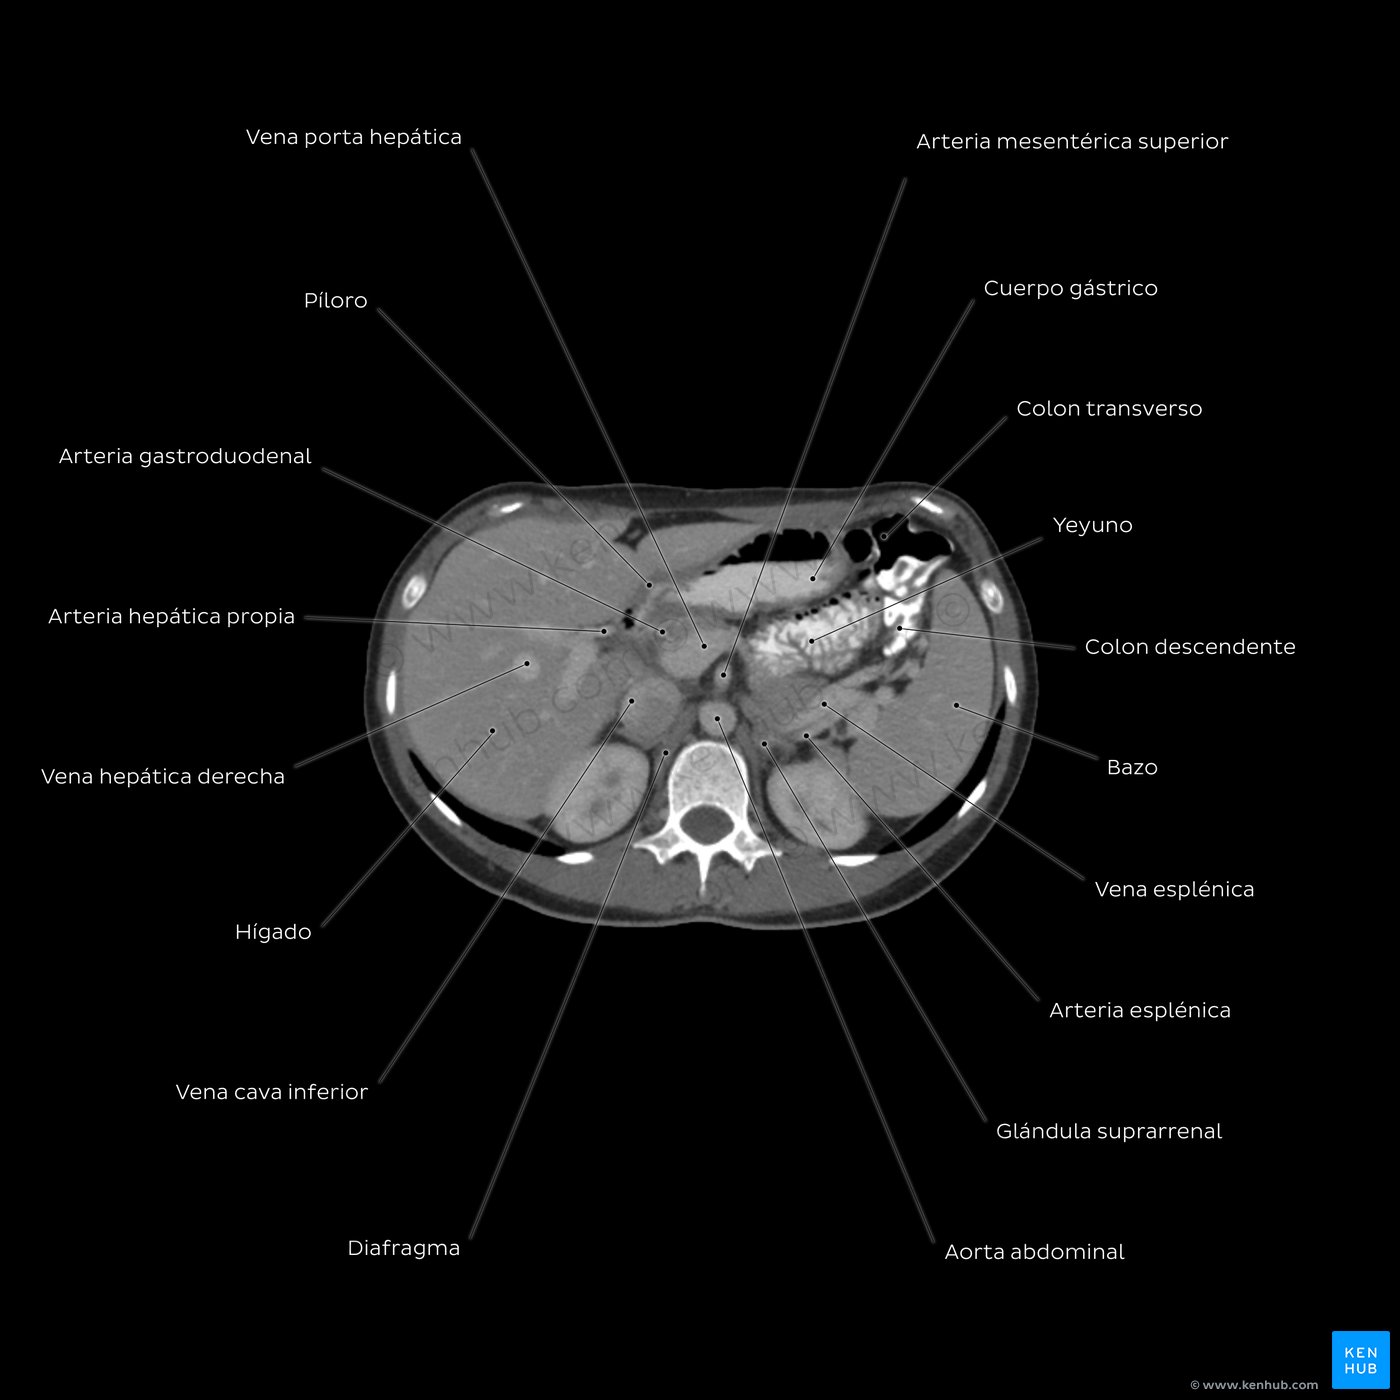

TC abdominopélvica

Junto con las radiografías, la TC es un método muy útil para examinar la anatomía del abdomen y la pelvis. La TC visualiza claramente los huesos, el aire, la grasa y los líquidos. Recuerda que el aire es negro, los huesos son blancos; y los tejidos blandos, los órganos y los fluidos tienen diferentes tonos de gris.

Comencemos analizando el anillo exterior que observas en gris; este representa la piel. Moviéndonos hacia adentro vemos la banda oscura de tejido subcutáneo. La siguiente capa de tejido gris son los músculos del tronco. Anteriormente deberías poder identificar los músculos abdominales; recto del abdomen, oblicuo externo e interno y transverso del abdomen. Posteriormente tenemos los músculos de la espalda; dorsal ancho, erector de la columna, cuadrado lumbar e iliopsoas. Incrustada entre los músculos posteriores se encuentra la vértebra L3 blanca (hiperdensa). Su cuerpo vertebral está separado del arco posterior por el canal vertebral gris.

Los órganos abdominales se encuentran situados más profundo con respecto a los músculos. Empecemos por los órganos sólidos. Puedes ver claramente el hígado; es gris y ocupa gran parte del espacio a la derecha del paciente. Ligeramente más hipodensa y recostada contra la porción anterior del hígado, podemos apreciar la vesícula biliar. A continuación vemos el páncreas; este órgano se muestra de color gris claro y está ubicado en el centro de nuestra tomografía computarizada. Moviéndose posteriormente, observa dos órganos emparejados, idénticos tanto en el lado izquierdo como en el derecho, estos son los riñones. Mira cómo la pelvis renal tiene un color gris más oscuro que el parénquima renal.

Ahora pasamos a revisar los órganos huecos, es decir, estómago, intestino delgado e intestino grueso. Estos órganos se encuentran llenos de aire, por lo que sus cavidades se aprecian en negro. Sus cavidades claramente delimitadas por paredes de tejido blando que se ven de color blanco. En el centro de la imagen podemos ver formas circulares en tonos grises que representan a los grandes vasos. Busca en esta imagen la vena cava inferior, la aorta abdominal, la arteria y vena renal.